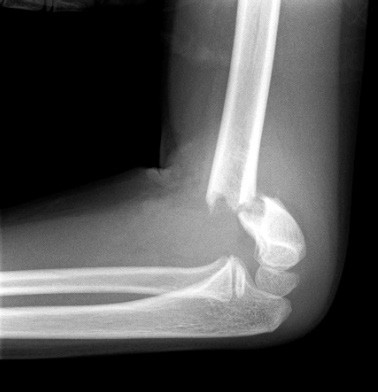

Supracondylar fractures

There is a weak spot above the humeral condyles at the level of the olecranon and coronoid fossae. Injuries here are typically FOOSH.

- X-rays: AP and lateral and a contralateral views of the elbow or both in cases of uncertainty. The Gartland Classification (Grade I–III) is used to grade these fractures.

I. Undisplaced fracture

Here one may only see the fat pad sign. The fat pad sign is appreciated on the lateral view X-ray. Usually, an anterior fat pad can be seen. The presence of a posterior fat pad on X-ray is abnormal.

II. Partially displaced with intact posterior periosteal hinge

If the anterior humeral line crosses the capitellum, no reduction is required, and management is as for Type 1.

III. Completely displaced fracture

Here there is a completely displaced fracture (See below: the anterior humeral line does not pass through the capitellum). There is a high risk of neurovascular injury (an orthopaedic emergency). These patients require urgent reduction and referral for operative management.